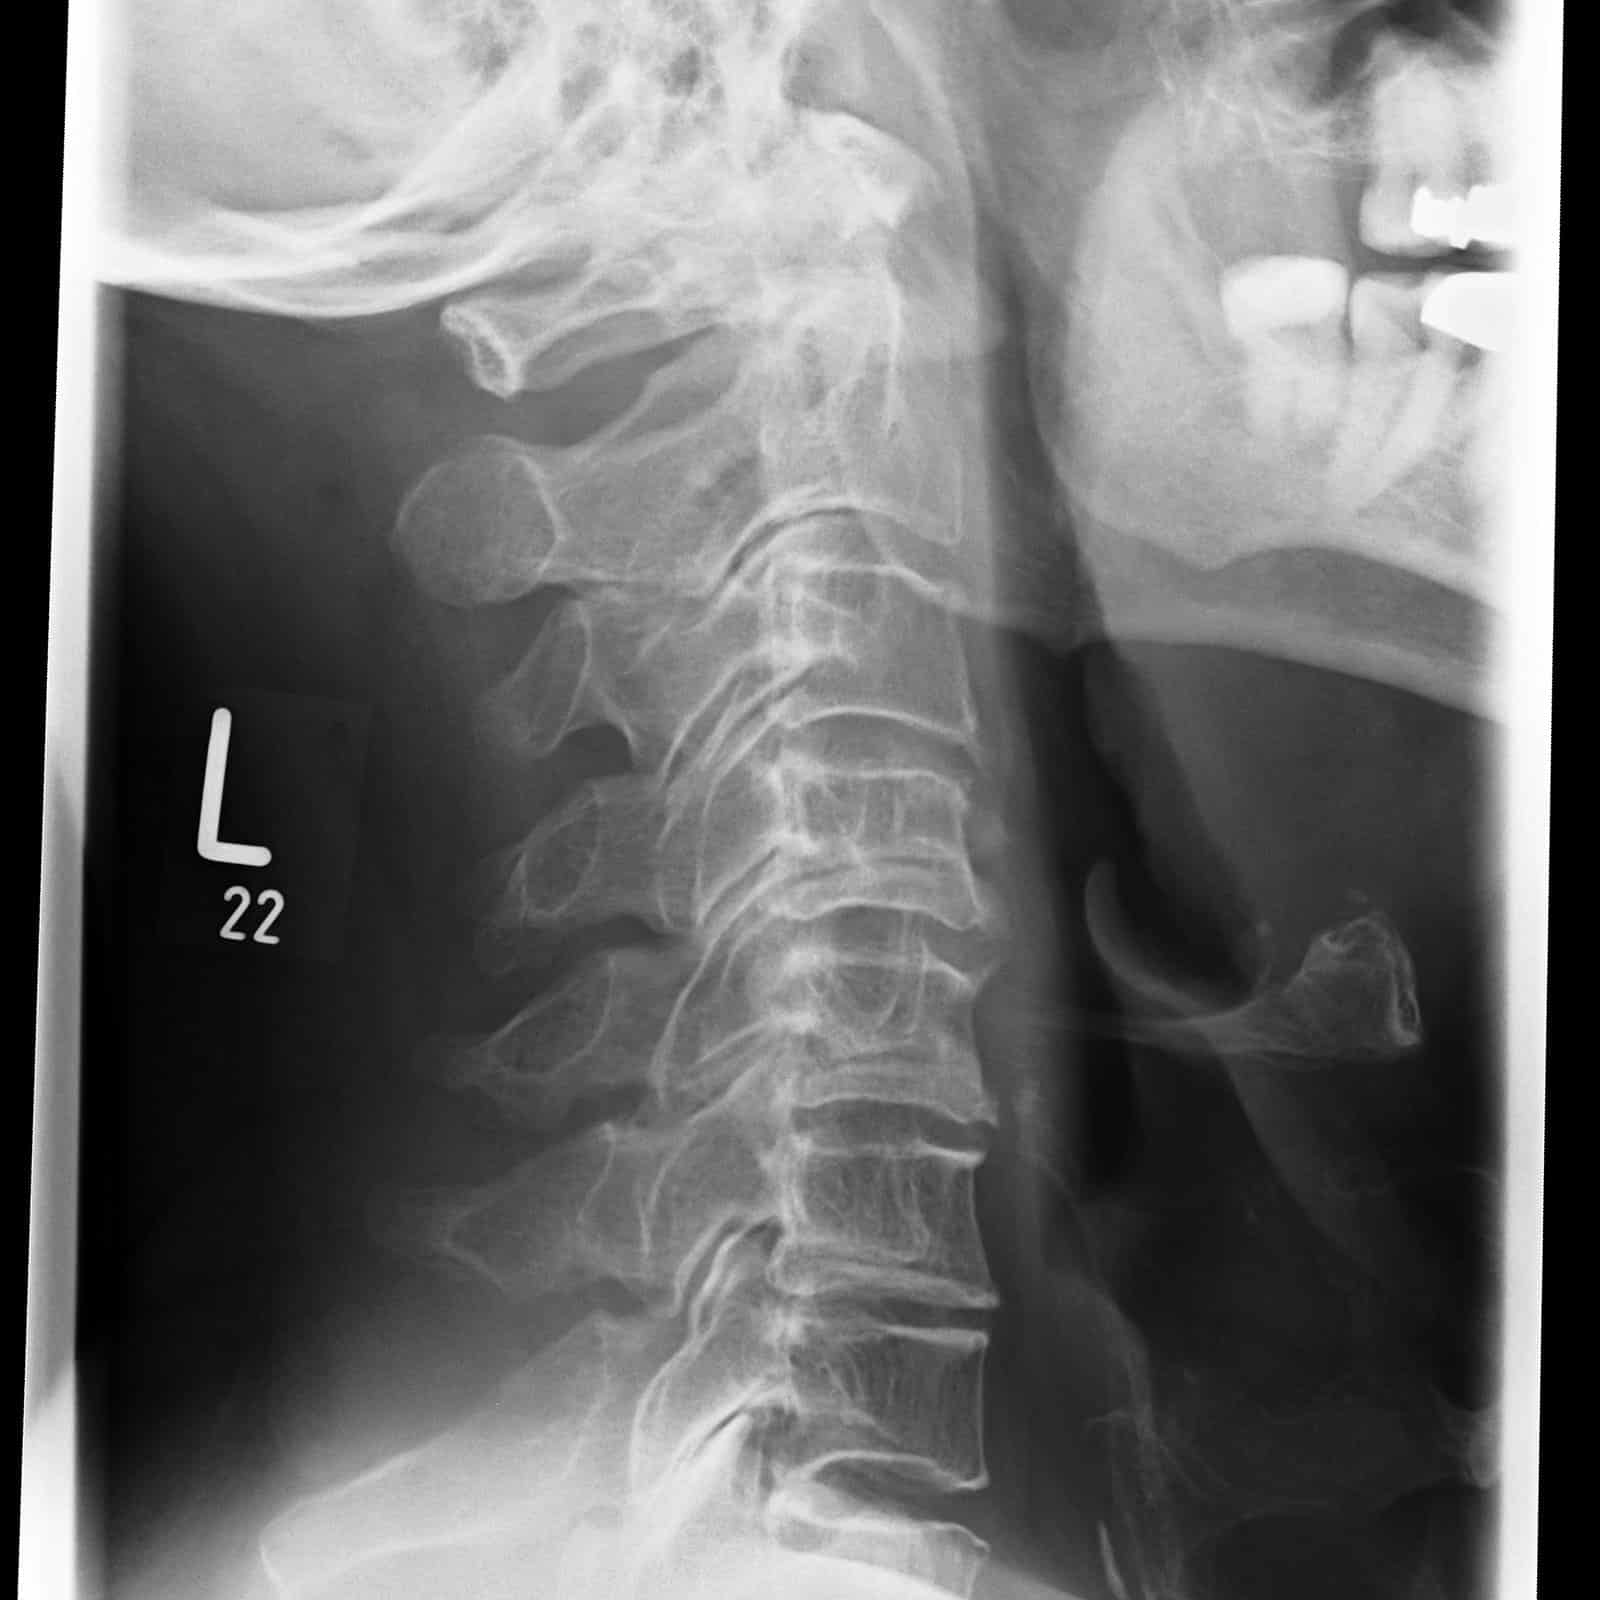

Die Schmerztherapie unter CT-Sicht ist eine prĂ€zise und schonende Methode zur gezielten Behandlung chronischer oder akuter Schmerzen. Durch die computertomographisch gesteuerte Bildgebung kann die Injektion von schmerzlindernden oder entzĂŒndungshemmenden Medikamenten exakt an die betroffene Stelle erfolgen, etwa an die Nervenwurzel oder das Facettengelenk der WirbelsĂ€ule.

Die Behandlung erfolgt in bequemer Liegeposition und dauert meist nur wenige Minuten. Nach einer örtlichen BetĂ€ubung wird eine feine Nadel unter CT-Kontrolle millimetergenau platziert. Anschließend wird das Medikament verabreicht, um Schmerzen gezielt zu lindern und EntzĂŒndungen zu reduzieren.

Ziel der Therapie ist die Schmerzleitung zu unterbrechen. Direkte Kortisongaben fĂŒhren an den Bandscheiben zu einem entwĂ€ssernden und damit abschwellenden Effekt mit nachfolgender Verringerung der mechanischen Nervenwurzelreizung durch Bandscheibenvorwölbung oder -vorfall.

• Vorbefunde: Um die Injektion prĂ€zise setzen zu können, benötigen wir unbedingt relevante medizinische Vorbefunde sowie aktuelle MRT- oder CT-Bilder. Ohne diese Unterlagen ist eine sichere und zielgerichtete Behandlung nicht möglich.